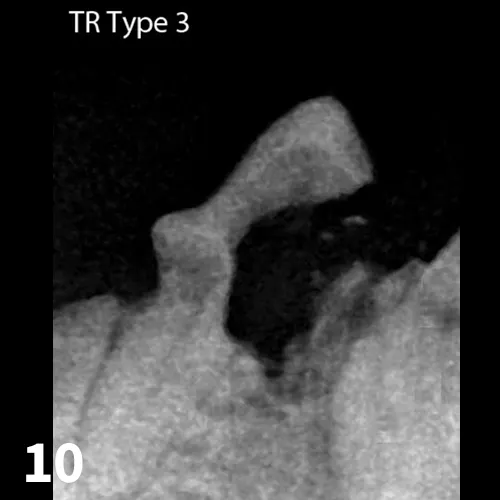

Three types of tooth resorption, which can only be diagnosed with dental radiographs, are seen. With Type 1, the periodontal ligament and the root remain normal, but there is destruction of the dental hard tissue. (See Figure 8.) With Type 2, the periodontal ligament and roots become indistinct as bone replaces them; with Type 2 lesions, it is evident that while resorption is destroying dental hard tissue,  osteoblasts are infiltrating the affected area. Over time, the root contour becomesmore irregular and bone completely replaces the root.12 (See Figure 9.) Teeth can be affected by both Type 1 and Type 2 resorption, which is known as Type 3. (See Figure 10.) The cause of tooth resorption is unknown, although links have been made to periodontal disease, mechanical trauma, immunosuppressive viruses, and increased vitamin A and D intake.11

FIGURE 8

Radiograph of tooth resorption Type 1: Note the hard tissue damage at the gumline even though the tooth roots look normal.

Figures 8, 9, and 10 courtesy of AVDC Nomenclature “Types of Resorption Based on Radiographic Appearance.” http://www.advc.org/nomenclature.html#resorption